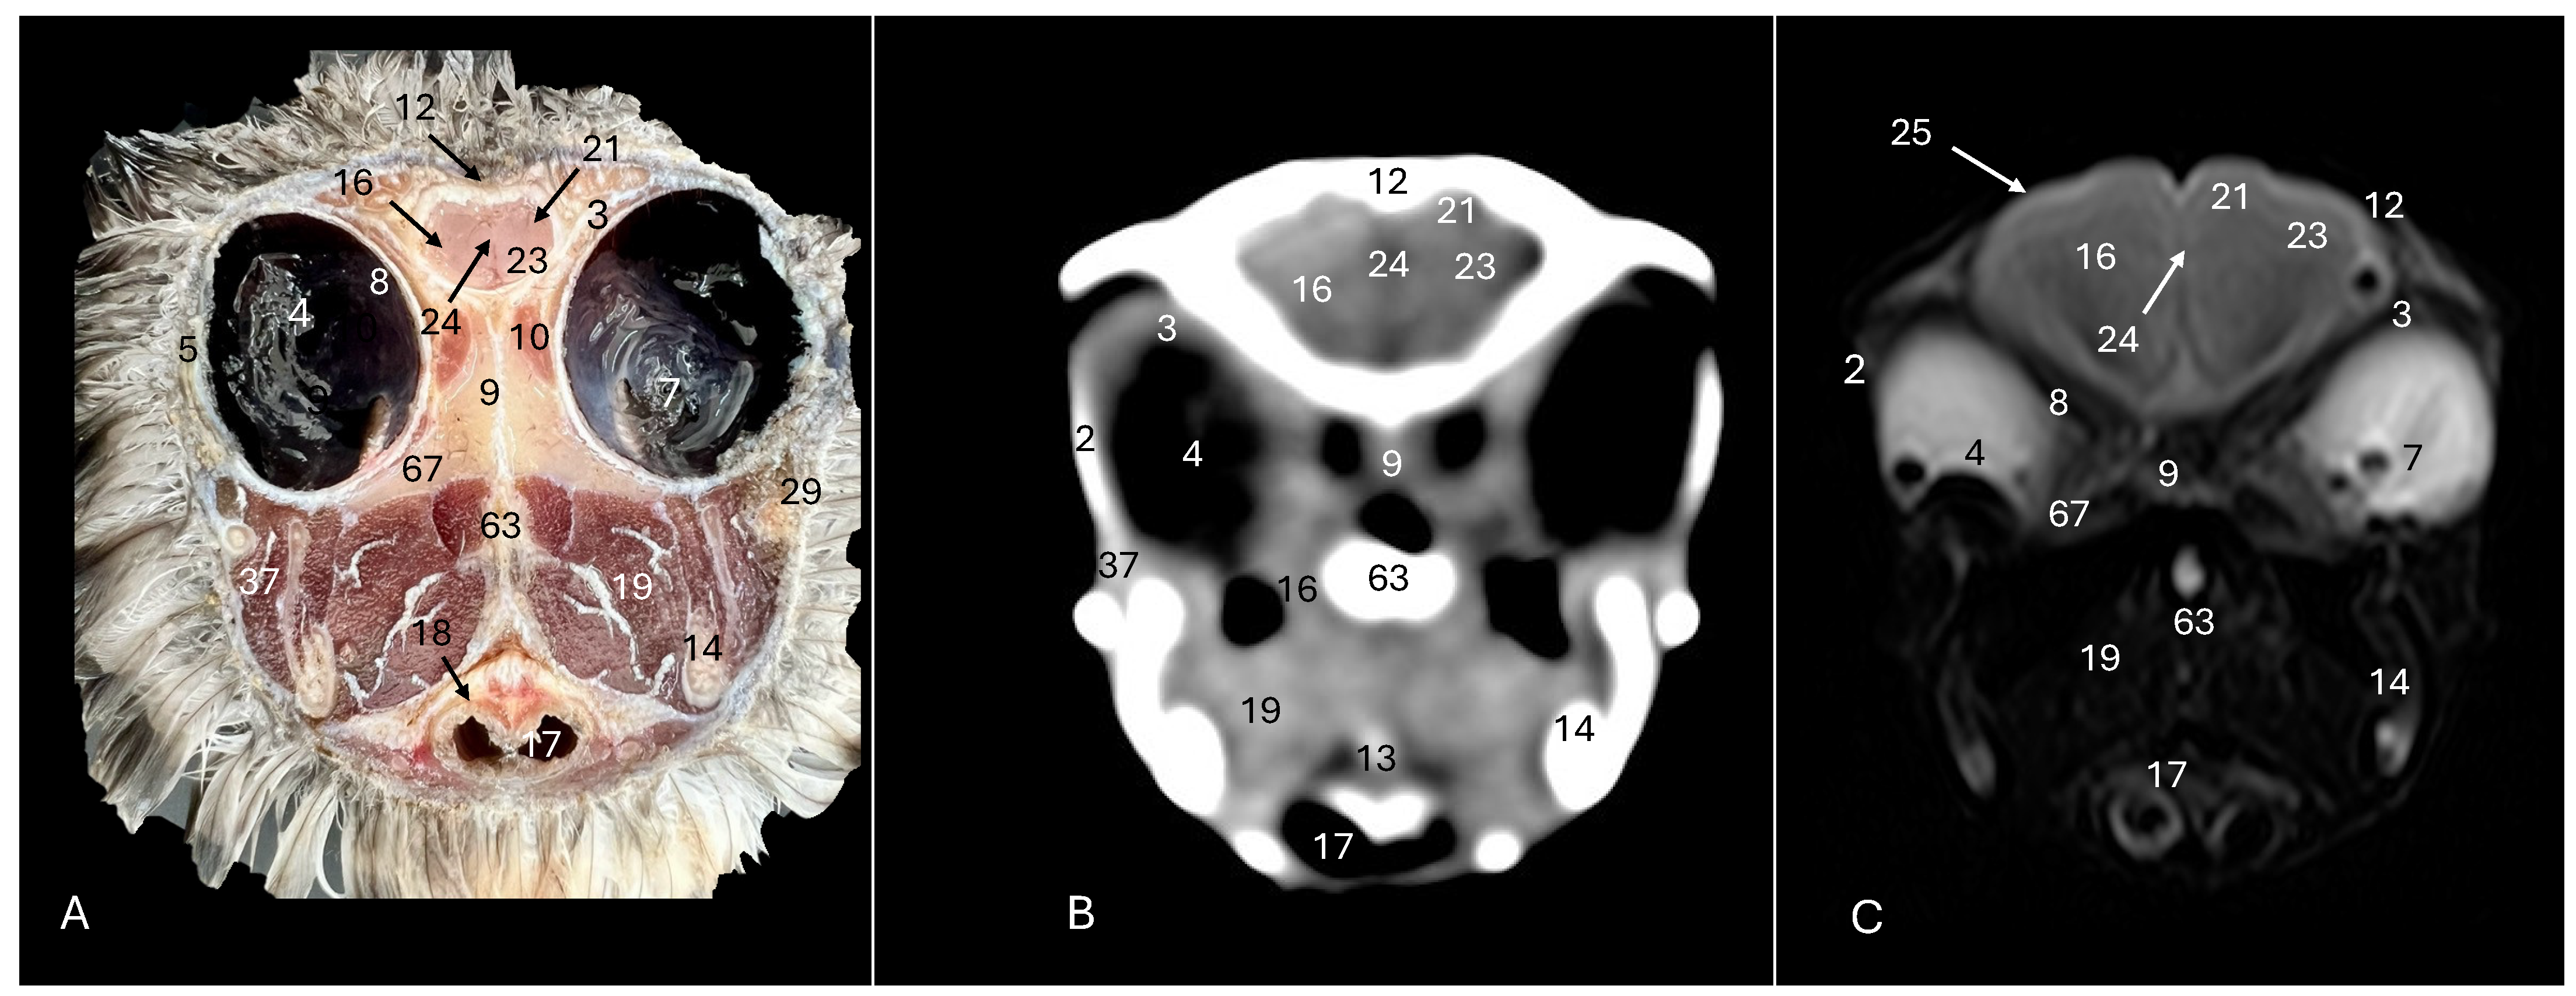

Figure 3. Anatomical cross-section (A), soft tissue CT window (B) and T2-weighted MR (C) transverse images of the Cory’s shearwater head at the level of the hyperpallium, corresponding to line II in Figure 1. 2: Sclerotic ossification; 3: sclera; 4: camera vitrea bulbi; 5: cornea; 7: pecten oculi; 8: retina; 9: septum interorbitalis; 10: extraocular muscles; 12: os frontale; 13: pharynx; 14: mandible; 16: cerebral hemisphere; 17: trachea; 18: tracheal ring; 19: musculus pterygoideus pars ventralis; 21: Hyperpallium; 23: vallecula telencephali; 24: fissura longitudinalis cerebri; 25: meninges; 29: processus postorbitalis; 37: musculus adductor mandibulae externus; 63: parasphenoid rostrum; 67: os pterygoideus.